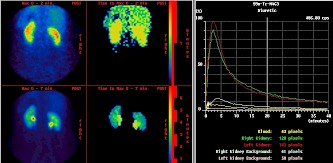

Bild rechts: Auswertungssoftware für eine MAG3 gestützte Nierenszintigrafie

Quelle: http://www.dr-w-koch.de

Danke für die Errinerung. :)Heute verwenden wir fast ausschließlich 99m-Tc-MAG-3 für die Nierenszintigraphie. Am häufigsten ist die Fragestellung einer Abflüßstörung und eingeborene Fehlbildungen der Nieren. Zweithäufig - seitengetrennte Nierenfunktionsbeurteilung vor Radiatio oder OP.Seltener kommen die Nierenspender. Welche Fehlerquellen sind bei der Untersuchung zu beachten und wie konnte man die Fehlern vermeiden?